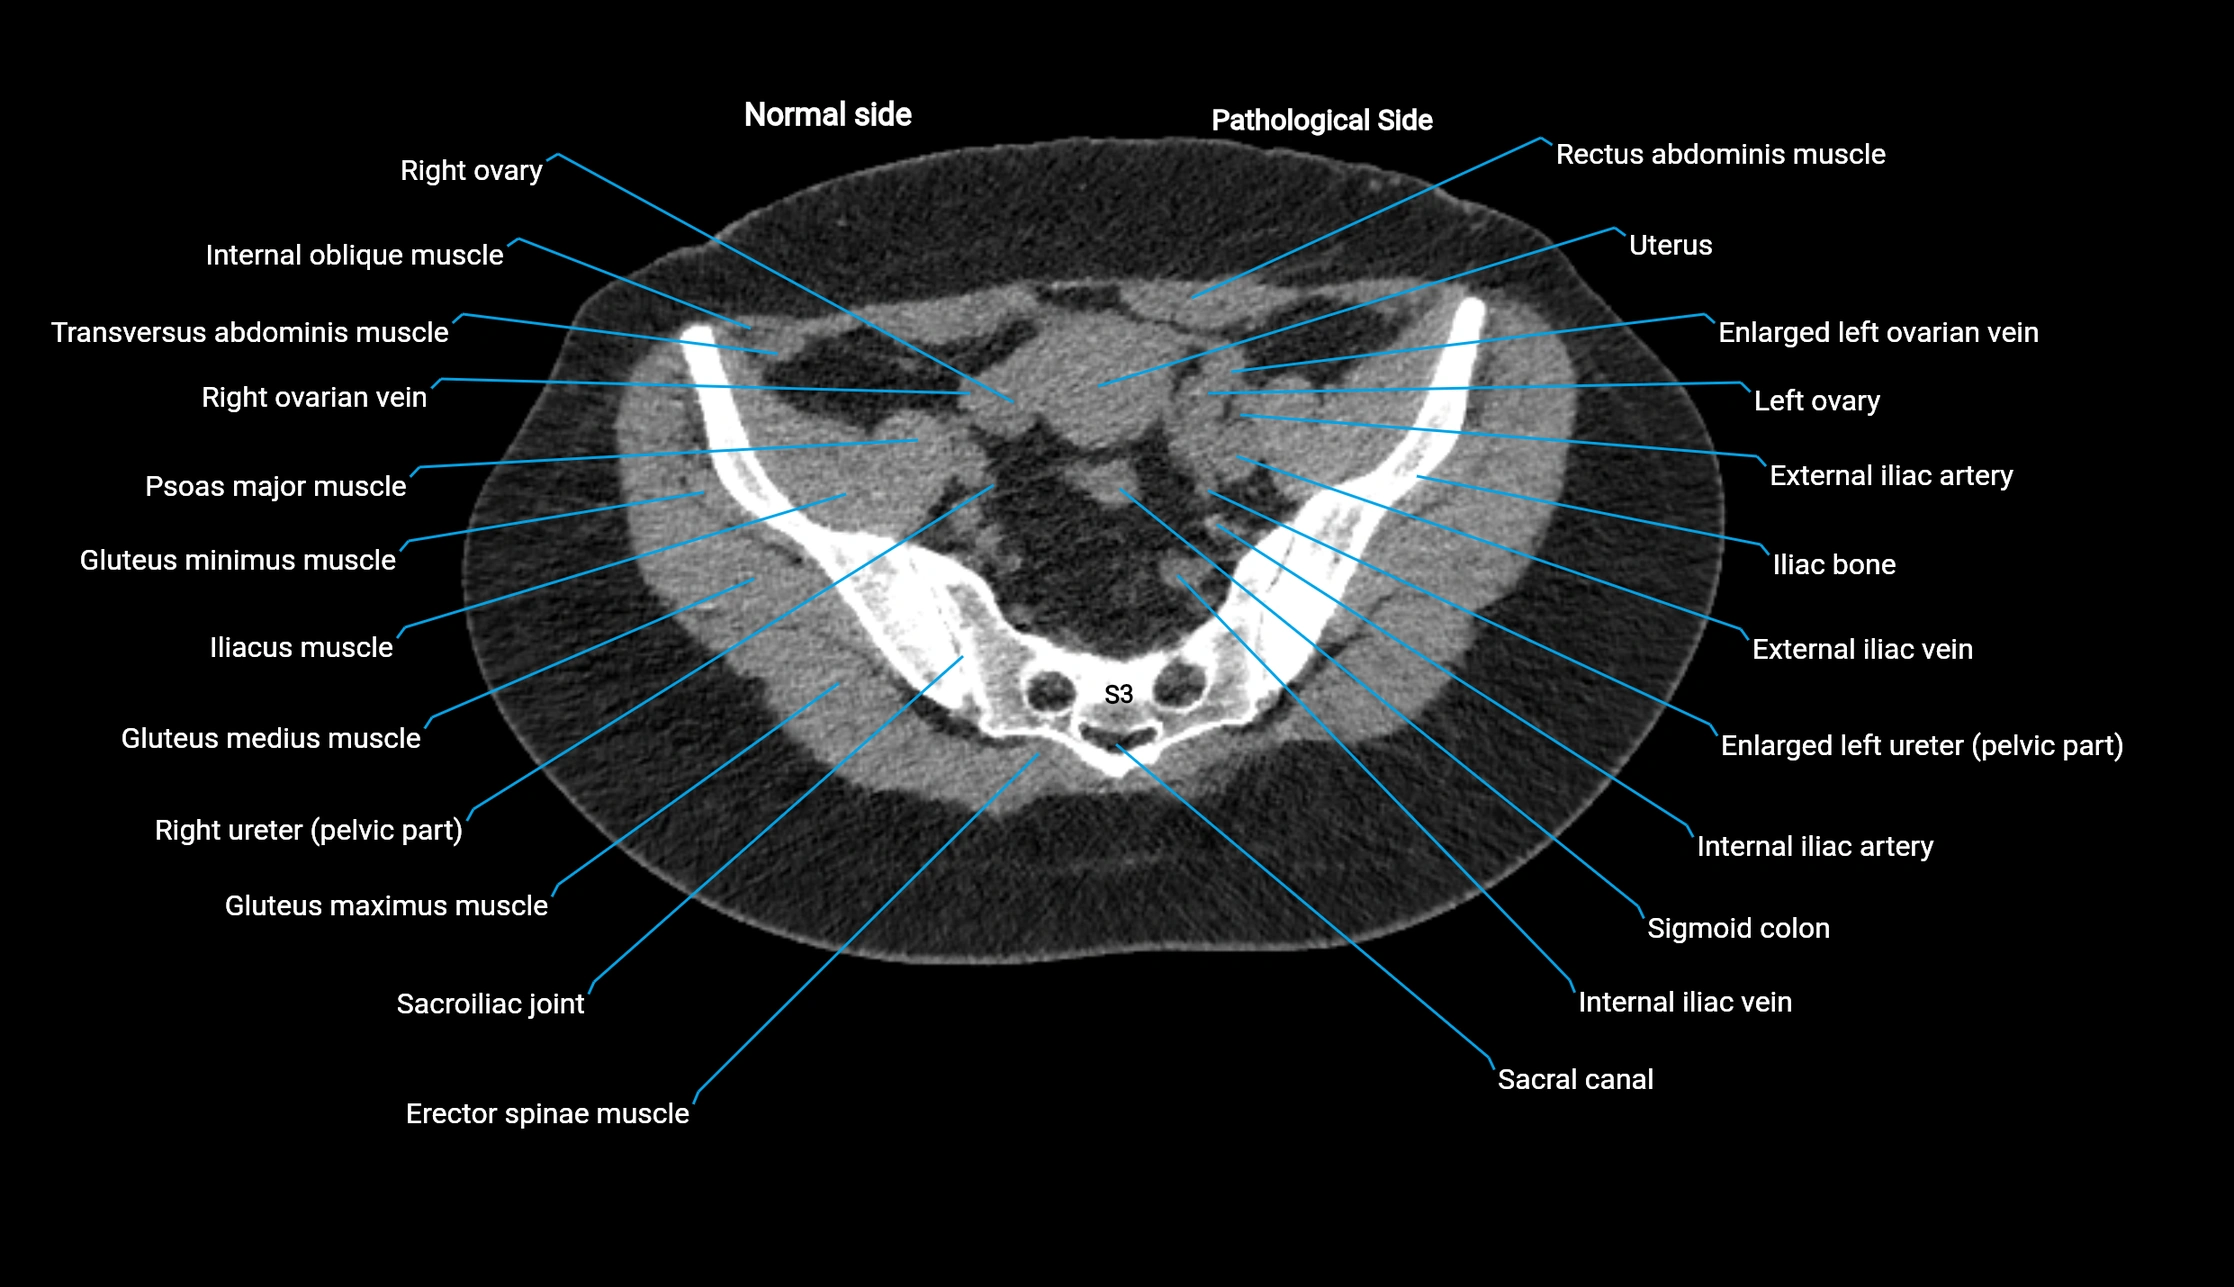

CT image

image